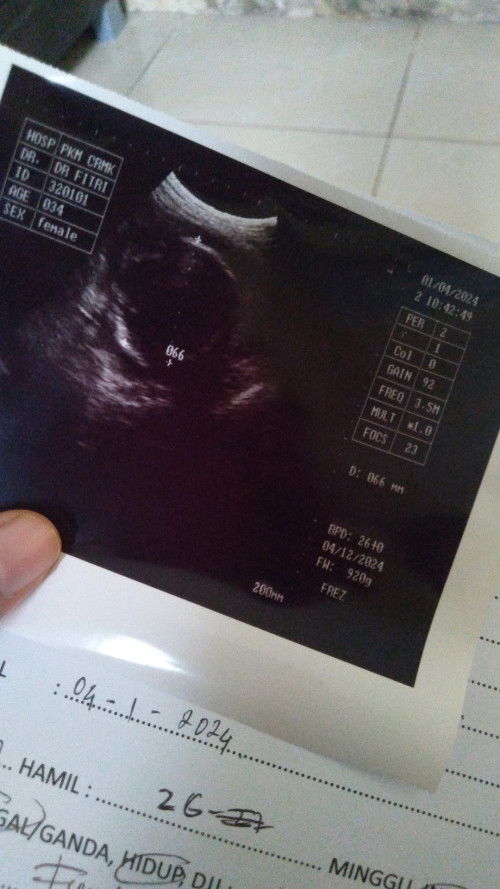

Haii bund.mau tanya dong, ada yang tau? maksud sex female disini untuk janin atau drnya ya? 🙏

Kayanya jenis kelamin dokternya si dr.Fitri itu bund..